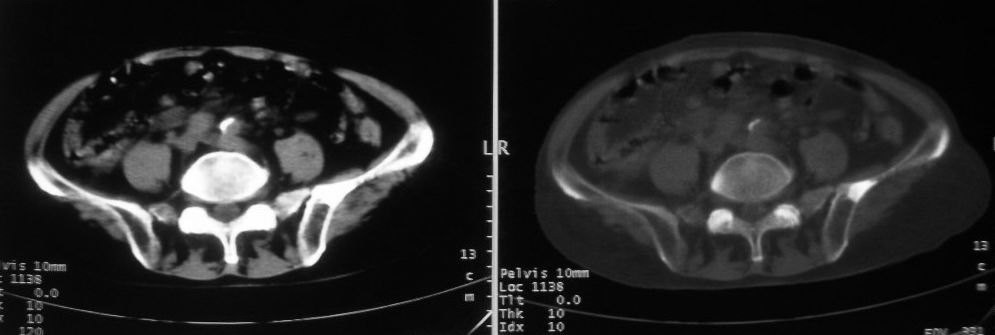

以下是引用zjzjr在2008-10-3 12:59:00的发言:[br]前列腺癌伴左髂骨\\腰椎转移可能性大.

以下是引用卜一在2008-10-3 13:40:00的发言:[br]前列腺癌!左髂骨\\腰椎转移?建议行全身骨扫描!

以下是引用深泽交通医院在2008-10-3 15:33:00的发言:[br]前列腺实性增大伴分叶状,与包膜间隙境界不清;椎体松质区间结节样密度影,考虑:前列腺癌,并椎体成骨性转移